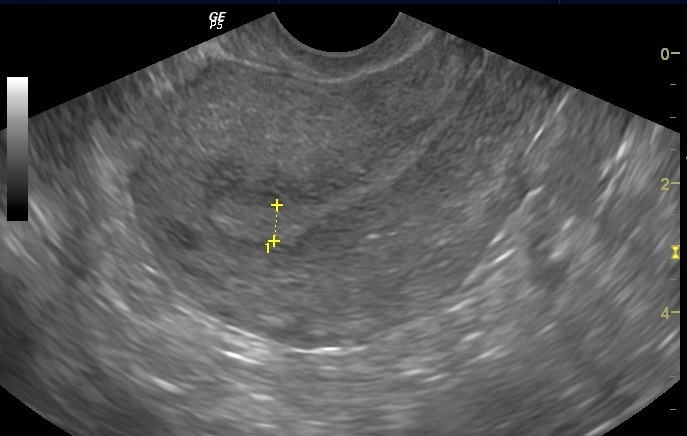

Evaluation of the Uterine Cavity

Evaluation of the uterine cavity is an important part of fertility testing. The uterus is where a pregnancy should implant and grow; issues within the uterus are associated with infertility, pain during pregnancy, preterm delivery, and miscarriage.

A transvaginal ultrasound is often the first step in a uterine evaluation. It can be used to check for the presence of fibroids, abnormalities of the uterine lining, and other uterine pathologies such as certain Mullerian anomalies and endometriosis within the uterine wall (adenomyosis). A saline-infusion sonohysterogram (SIS) can be used to further delineate the uterine lining and see subtle issues with the cavity, including uterine polyps (common, benign overgrowths of the uterine lining). If left untreated, polyps may increase a woman’s risk of infertility and miscarriage. A SIS can also give a clearer view of the uterine shape, and can help determine if a fibroid (benign tumor of the uterine musculature) needs to be removed.